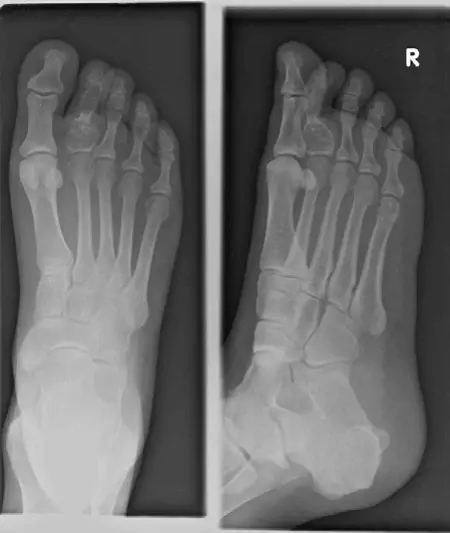

* العظام الصغيرة لليدين والقدمين: مثل السلاميات (phalanges) وعظام المشط (metacarpals) وعظام الأمشاط (metatarsals). تُعد هذه المنطقة الموقع الأكثر شيوعًا على الإطلاق.

الأشعة السينية العادية (Plain X-rays)

- الأهمية: غالبًا ما تكون الأشعة السينية هي الفحص الأولي الذي يكشف عن الورم.

- الميزات النموذجية:

- آفة شفافة (Lucent Lesion): تظهر كمنطقة داكنة في العظم، مما يشير إلى أنها أقل كثافة من العظم المحيط.

- تكلسات نقطية أو حلقية قوسية (Punctate or Rings-and-Arcs Calcifications): هذه هي السمة المميزة للأورام الغضروفية، حيث تظهر كبقع بيضاء صغيرة أو أنماط دائرية داخل الآفة، وهي تعكس وجود مادة غضروفية متكلسة.

- حدود واضحة ومحددة: غالبًا ما تكون الآفة محاطة بحدود واضحة أو "حافة متصلبة" (Sclerotic Border)، مما يشير إلى طبيعتها الحميدة وبطء نموها.

- غياب رد الفعل السمحاقي (Absence of Periosteal Reaction): عدم وجود نمو عظمي جديد على السمحاق (الطبقة الخارجية للعظم) يُعد علامة جيدة تدعم الطبيعة الحميدة.